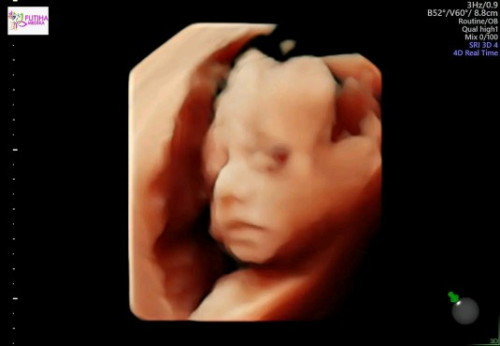

padahal baru hasil usg,kenapa kelihatan goodloking banget ya,bening banget hasil usgnya